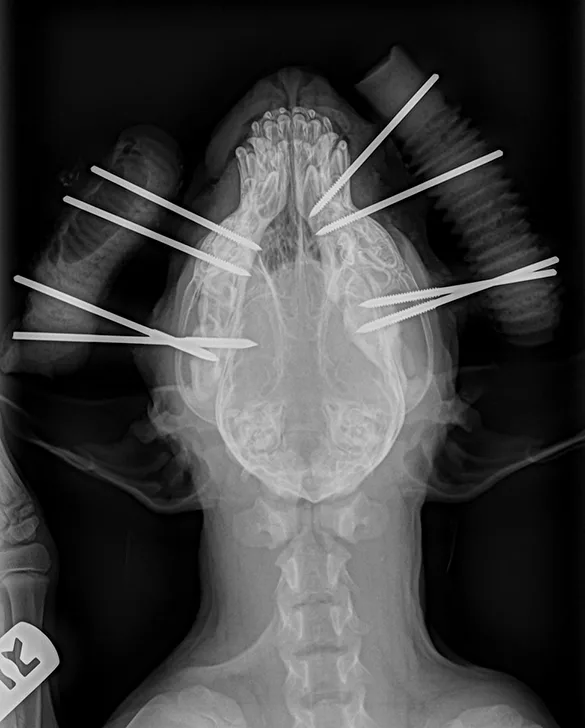

Close-up of dog’s head in dorsal recumbency with pharyngostomy tube and interdental wiring in place.

Pharyngostomy tube placement in a dog

General anesthesia is required for fracture treatment, and local anesthetic blocks are advantageous. IV antibiotics should be administered in patients that have open fractures. Intubation with a short endotracheal tube and pharyngostomy are useful for evaluating occlusion during fracture surgery; in the former, the connection between the tube and anesthesia hose is located in the mouth, allowing for brief, intermittent disconnection with closure of the mouth to assess interdigitation of the maxillary and mandibular teeth. A pharyngostomy tube can be placed caudal to the mandible through a separate skin and pharyngeal incision (Figure 1) or through an incision ventrolateral to the tongue.3